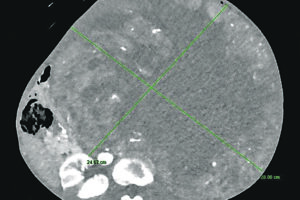

Un intervento multidisciplinare straordinario ha risolto un caso clinico del tutto eccezionale salvando la vita a una donna di 70 anni. Alla paziente è stata asportata nei giorni scorsi al Cardarelli di Campobasso una massa tumorale del peso record di oltre 15 chilogrammi. La 70enne si era rivolta al professor Guido Sciaudone, direttore della Chirurgia generale dell’ospedale di Campobasso che[Leggi di più…]